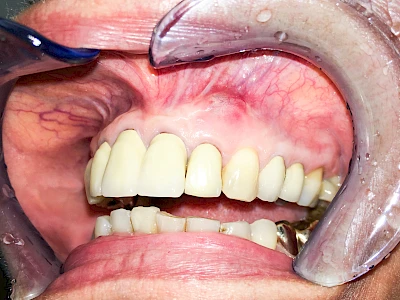

Diese Vermehrung von Bindegewebe in einem frei gewordenen Raum ist eine Sonderform der Anpassungsreaktion menschlicher Zellen und wird als Vakatwucherung bezeichnet.

Früher wurden im Unterkiefer mitunter Brücken zum Ersatz fehlender Zähne als sogenannte "Schwebebrücken" gestaltet. Die Idee dabei war, dass man die Brücke insgesamt besser reinigen kann. Allerdings war das für die Patienten mitunter irritierend für die Zunge und vor allem beim Essen gewöhnungsbedürftig. Teilweise haben sich hier reaktiv Vakatwucherungen der Kieferkammschleimhaut gebildet und den Raum unter der Brücke wieder verschlossen.